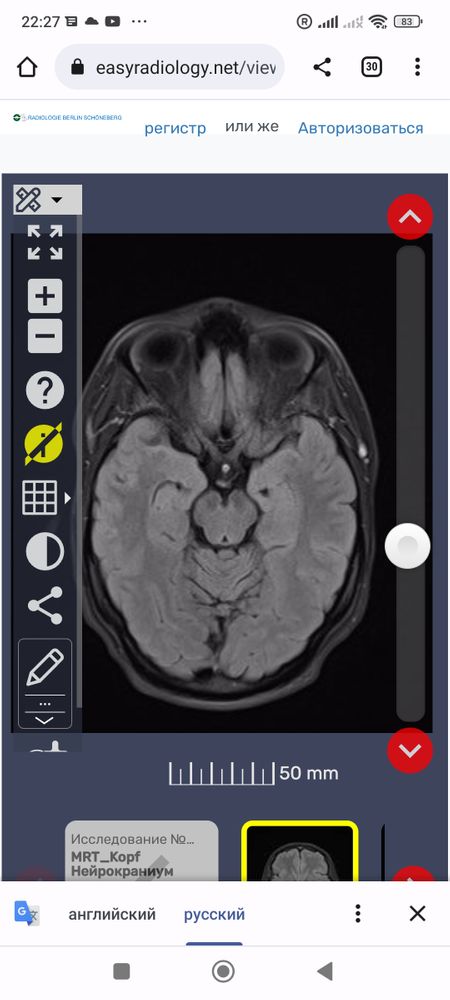

Что это за белые точки вокруг мозга? И все ли впорядке